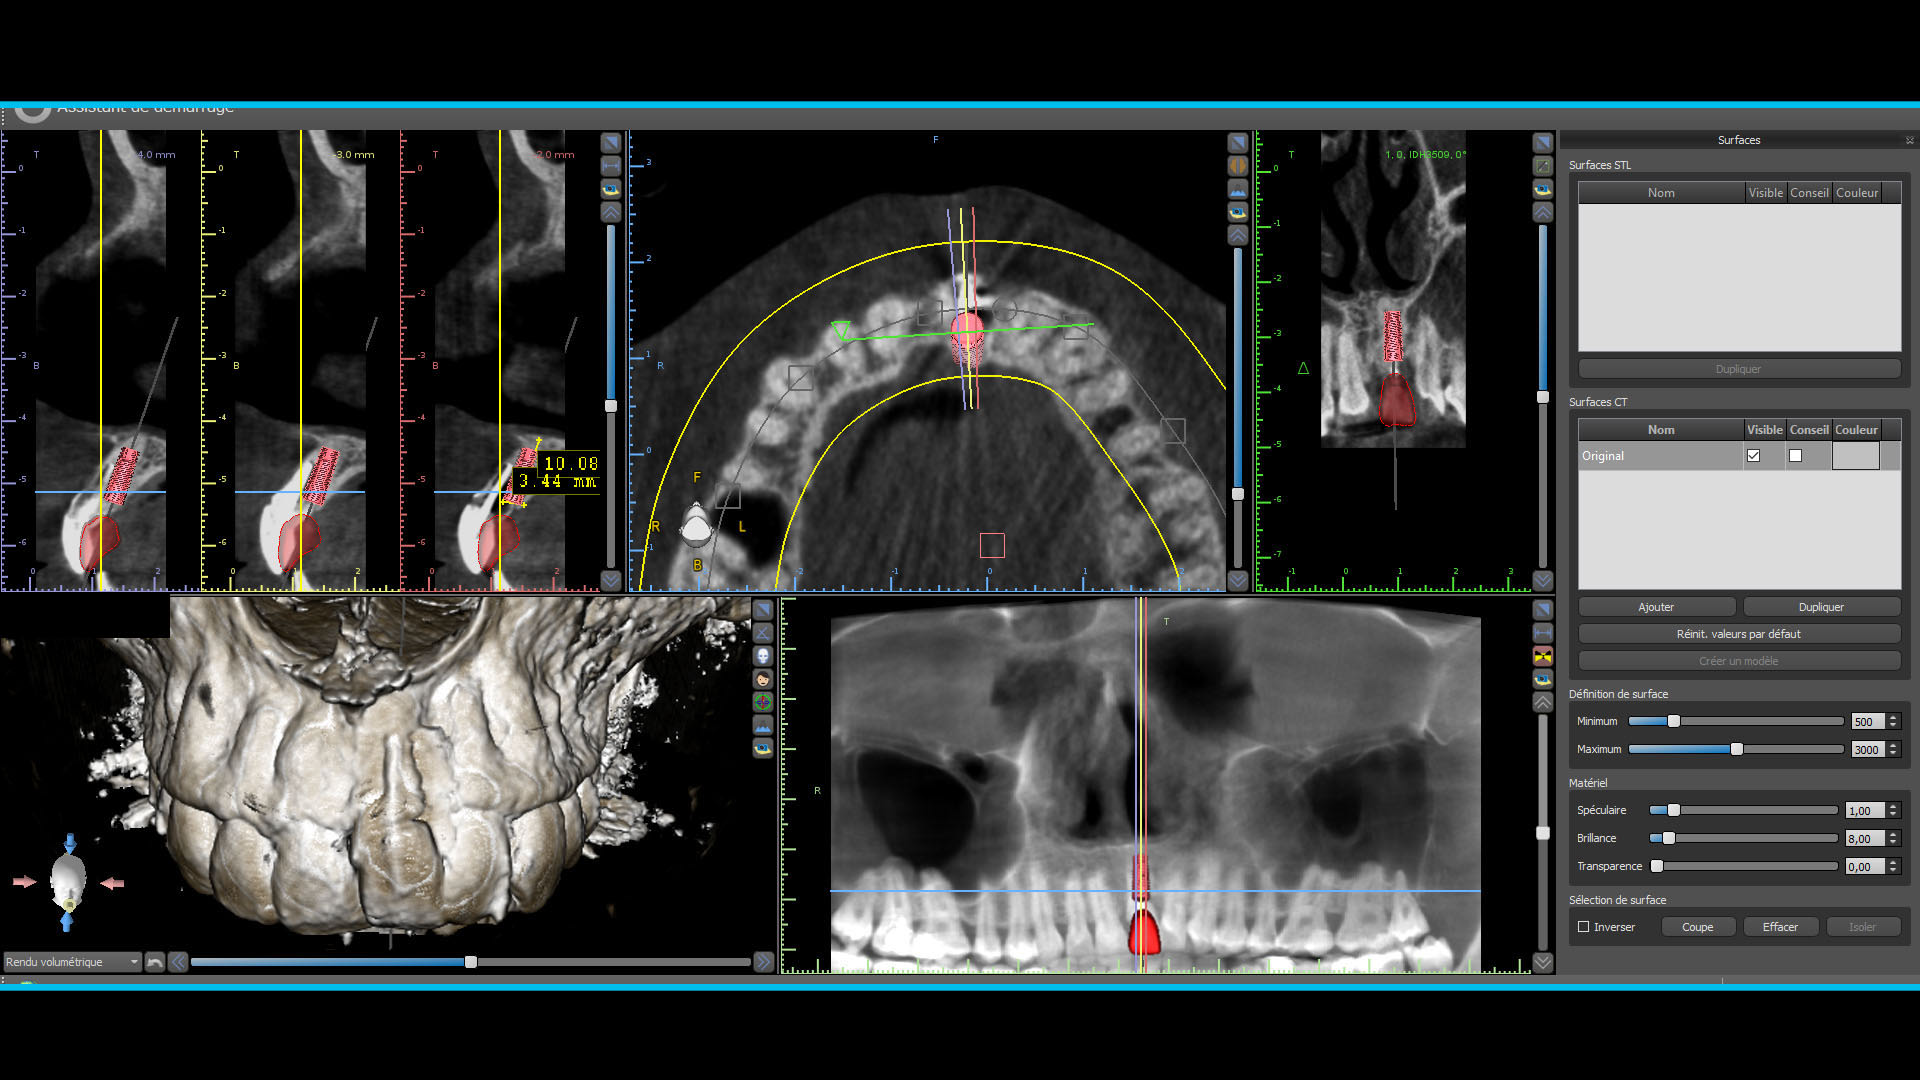

Quelques images du cone beam et de la planif

Planif 1 owxhvi - Eugenol

Planif 2 slmeas - Eugenol

Planif 3 v71j9j - Eugenol

Planif 4 my2dza - Eugenol

Planif 5 fqtf2p - Eugenol

Planif 6 ody3rj - Eugenol

tu n'as pas un cone beam avant implantation?

Non je n'en avais pas refait faire.

J'avais levé un lambeau pour l'extraction de la 21 donc j'avais déjà vu le site, et avant l'opération j'avais revu la patiente et "sondé" à l'aiguille.

Euh... ton implant est très très enfoui esthétiquement je pense que ça va pas être une super surprise (même si elle recouvre, pense que les patients regardent toujours en soulevant la lèvre...) ensuite par rapport à l'apex de ta 11 il semble très haut, je ferai une 3D perso pour voir mon plancher des fosses nasales.

@Zuhurragin : non je suis certain qu'il n'y a pas eu de perforation du plancher nasal, j'ai sondé le forage implantaire.